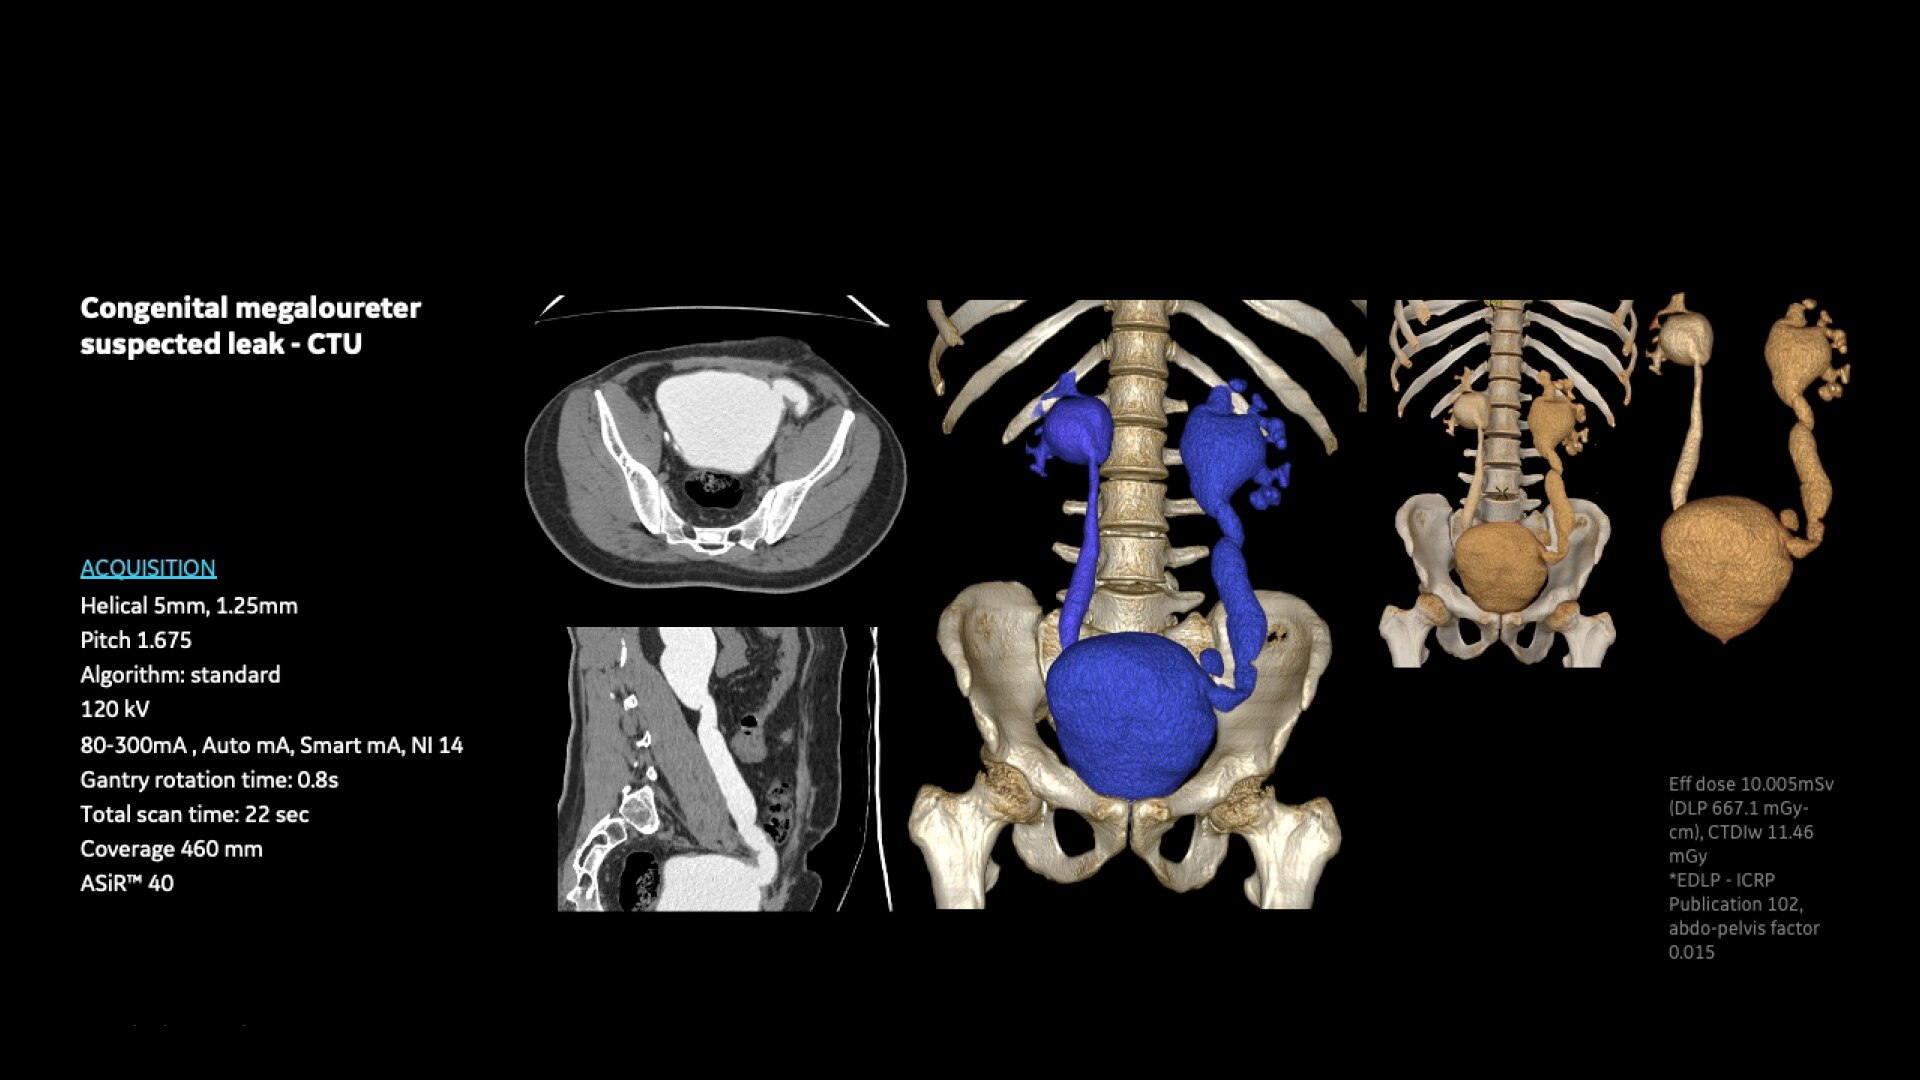

Revolution Aspire offers a full range of innovative imaging software

Volume Viewer – Provides information about the spatial relationships using volume rendering, multi-planar reformat, and MIP/min-MIP.

Navigation and Fly-through – Uses Virtual Endoscopy to visualize intraluminal structures and view images dynamically.

Vascular Imaging and Processing – Enhances analysis of vascular features by automatically determining vessel centerline and tracking multiple vessels.